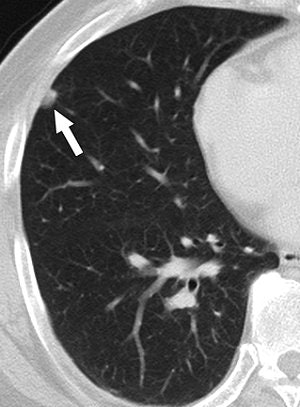

| A 58-year-old man with squamous cell carcinoma in right upper lobe and biopsy-proven anthracofibrotic nodule in lobe not containing primary tumor. Transverse lung-window CT scan at level of basal segmental bronchus shows 9-mm subpleural nodule (arrow) in right middle lobe. Nodule was pathologically proven anthracofibrotic nodule. |